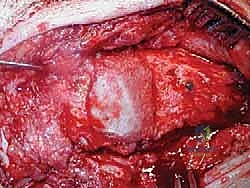

الخطوة الثالثة: إزالة المفصل القديم (Explant Removal)

يتم استخراج المكونات المعدنية والبلاستيكية لمفصل (Agility) القديم بحرص بالغ للحفاظ على ما تبقى من العظم السليم.

الخطوة الرابعة: تنظيف العظم والترقيع (Debridement and Bone Grafting)

يتم تنظيف الأنسجة الملتهبة والأكياس العظمية. ونظراً لأن مفصل (Agility) يترك فراغاً كبيراً بعد إزالته، يتم استخدام طعوم عظمية (Autograft من حوض المريض أو Allograft من بنك العظام) لملء الفراغات وبناء أساس قوي.